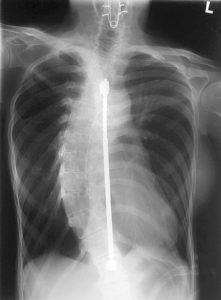

Scoliosis is diagnosed in a very specific manner. Typically, the doctor will obtain a family history, since scoliosis has shown a significant genetic link. Chances are, if your child has scoliosis, a sister, brother, parent, or grandparent also has it to some degree. Once you family history is taken, certain orthopedic tests are conducted, such as an Adam’s forward bending test. This test shows if there is a rib hump present on one side of the spine. The only true objective means, however, for determining if your child has scoliosis is by taking spinal x-rays. The scoliosis is measured at the top and bottom of the curvature by a geometrical measurement called Cobb’s angle. Conventional medicine proposes that a scoliosis below 20° typically does not need to be treated, especially if there are no symptoms present.

Patients with substantial spinal curvatures very often require an x-ray evaluation of the spine. The procedure helps determine the location and magnitude of the scoliosis, along with an underlying cause not evident on physical examination, other associated curvatures, and the health of other organ systems that might be affected by the scoliosis. In addition, x-rays of the wrist are often performed. These films help determine the skeletal age of the person, to see if it matches an accepted standard, which helps the doctor determine the likelihood of progression. Depending on the scoliosis severity, x-rays may need to be repeated as often as every 3 to 4 months to as little as once every few years.

Chiropractors use medical and family history, physical and neurological examination when checking a person for scoliosis. An X-ray will help to diagnose the scoliosis and lets the chiropractor measure the curve and see its location, shape and pattern. An early X-ray is useful to check for any subsequent increase in curvature later on.